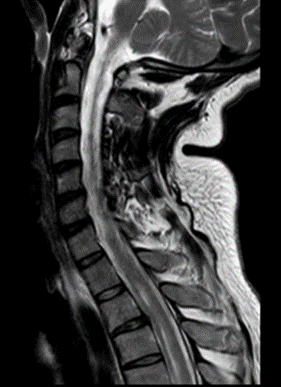

Se solicitó inicialmente Imagen de resonancia magnética (IRM) de columna lumbosacra simple y estudios de neurofisiología. La electromiografía más neuroconducciones de las 4 extremidades reportó neuropatía mielínica de expresión leve del nervio peroneo motor. Imagen de resonancia magnética lumbosacra simple muestra hallazgos compatibles con aracnoiditis adhesiva (figura 1). Ante estos hallazgos, se complementan estudios con resonancia torácica y cerebral con contraste. En la resonancia de columna torácica, se observa incipiente siringomielia (figura 2.) y la resonancia cerebral con contraste no mostró alteraciones.

Figura 2

Se toman imágenes de control observando progresión de processo inflamatório a nível cerebral y a nível lumbar (figuras 4 y 5), progresión de siringomielia com afectación a nível cervical (figura 6)

Figura 6